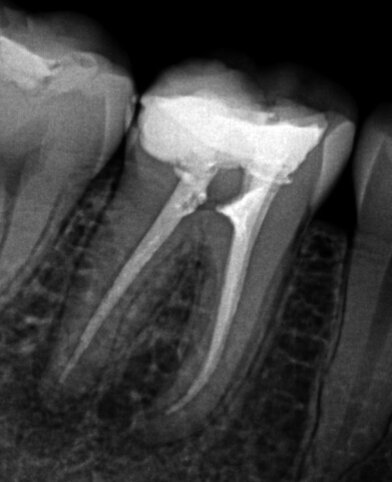

Fig. 1a: Debris left after root treatment of distal canal of a lower molar.

Fig. 1b: Radiograph of failed root canal treatment shown in Fig.1a.